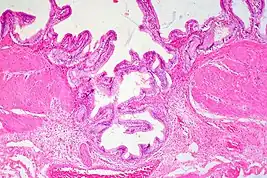

High magnification micrograph of uterine adenomyoma.

Histopathology of uterine adenomyosis. H&E stain.